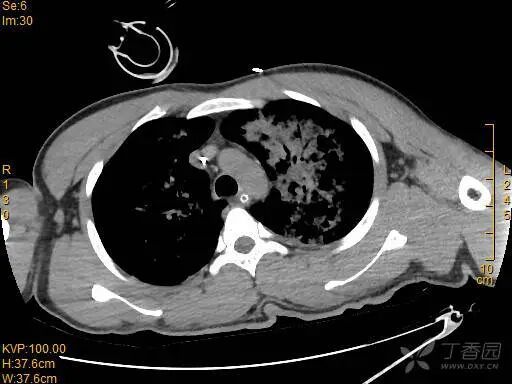

胸部 CT 如下:

图片